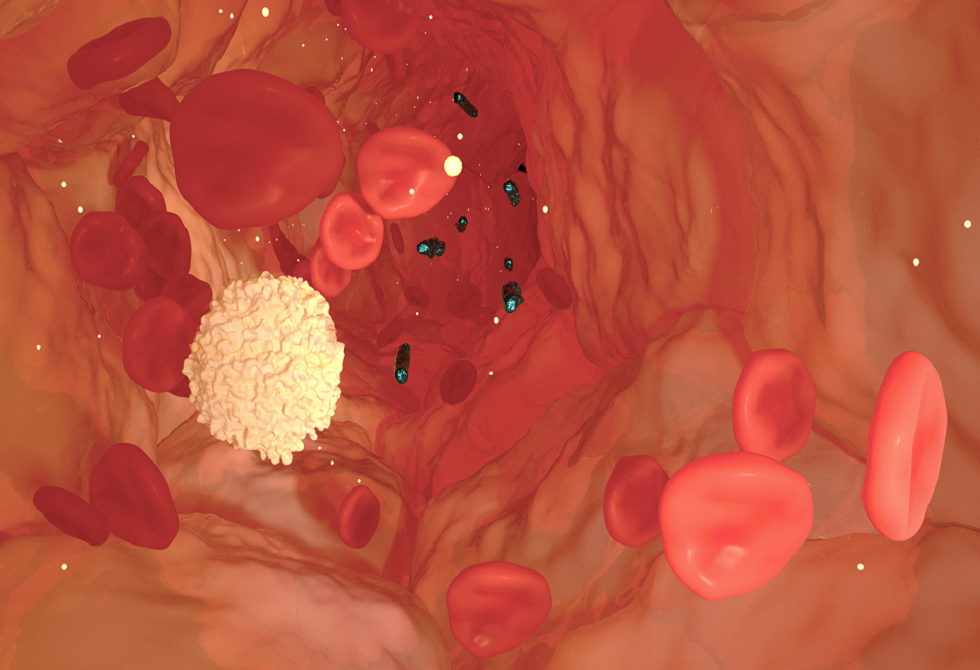

علاج محتمل جديد للإنتان

كشف باحثون من جامعة غريفيث عن نتائج علمية واعدة قد تمثل خطوة متقدمة في علاج الإنتان، بعد نجاح المرحلة الثانية من التجارب السريرية لدواء جديد، أُجريت في الصين.

ويعد الإنتان من الحالات الطبية الخطيرة التي تصيب ملايين المرضى في المستشفيات حول العالم سنويا، وينتج عن استجابة مناعية مفرطة للعدوى تؤدي إلى مهاجمة أنسجة الجسم وأعضائه، وقد تتطور إلى صدمة إنتانية وفشل متعدد في الأعضاء في حال عدم التشخيص والعلاج المبكرين.

وطوّر الباحثون دواء مرشحا لعلاج الإنتان يعرف باسم STC3141، وهو جزيء صغير قائم على الكربوهيدرات، وذلك بالتعاون بين البروفيسور مارك فون إيتزستين وفريقه من معهد الطب الحيوي وعلم السكريات في جامعة غريفيث، والبروفيسور كريستوفر باريش وفريقه من الجامعة الوطنية الأسترالية.

وأظهرت نتائج التجربة قدرة الدواء على الحد من الإنتان لدى البشر، بعد تحقيقه الأهداف الرئيسية للدراسة، بحسب ما أكده البروفيسور إيتزستين.

وأُعطي الدواء عبر الوريد بواسطة أنبوب صغير، بحيث يتدفق الدواء ببطء إلى الدم، حيث نجح في مواجهة ظاهرة إطلاق الجزيئات البيولوجية الكبيرة التي تحدث في الجسم خلال تطور الإنتان، ما يساهم في تقليل تلف الأعضاء وعكس آثاره. (عند حدوث الإنتان، يفرط جهاز المناعة في ردّة فعله، فيبدأ الجسم بإطلاق كميات كبيرة من مواد حيوية كبيرة الحجم إلى مجرى الدم. هذه المواد لا تكون ضارّة في الأصل، لكنها عندما تُطلق بكثرة وبلا ضبط تسبب التهابا شديدا وتلفا في الأعضاء).

وشملت المرحلة الثانية من التجربة، التي نفذتها شركة "غراند فارما" (Grand Pharma)، 180 مريضا مصابا بالإنتان، في ظل غياب علاج محدد لهذا المرض حتى الآن، ما يجعله من أبرز الاحتياجات الطبية غير الملبّاة عالميا.

وأفاد إيتزستين بأن الشركة تعتزم الانتقال إلى المرحلة الثالثة من التجارب السريرية لمواصلة تقييم فعالية العلاج الجديد وسلامته.

وأضاف: "نأمل أن يصبح هذا العلاج متاحا في الأسواق خلال السنوات القليلة المقبلة، بما قد يساهم في إنقاذ ملايين الأرواح".